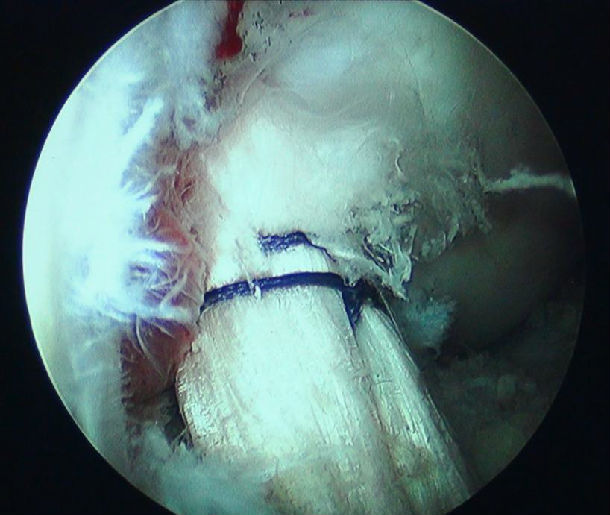

前交叉韧带如何重建?

610x515 - 51KB - JPEG